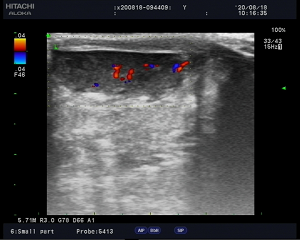

随着治疗的推进,所有关心患儿的人终于放下心来,患儿最后一次检查是在8月18日10:17分,检查结果对比上两次,明显好转,小朋友开心的喊道“可以回家了”。走出彩超室时,他开心的朝着医生挥手告别,一声声“谢谢,医生”在整个科室回荡。要知道切除睾丸对一个男孩子而言不仅是生理上的影响,更大的是心理上的影响。

(8月18日,睾丸未见明显转向,可见明显血流信号,睾丸扭转完全排除)